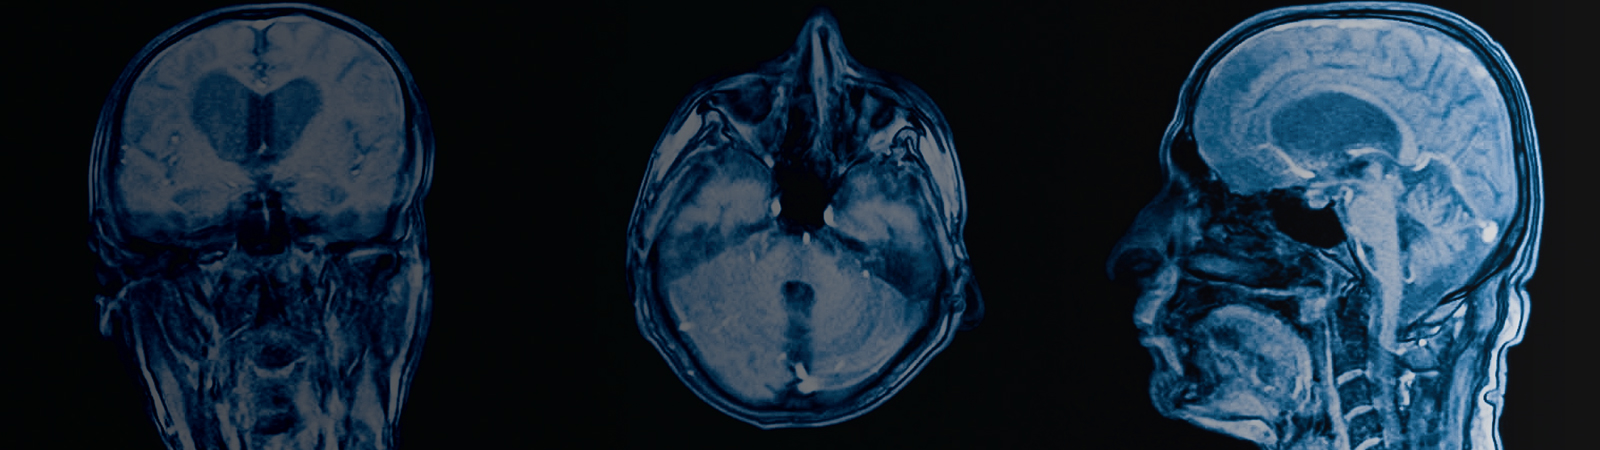

Neuro-Oncology

Brain and spinal tumors whether primary (arisinf from within the brain) or metastatic (coming from a remote source in the body).